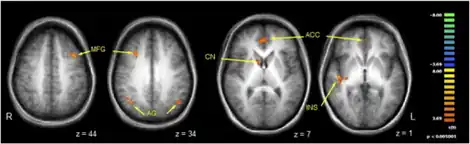

There has been much recent interest in using functional neuroimaging to study conversion. As researchers identify the mechanisms which underlie conversion symptoms, it is hoped they will enable the development of a neuropsychological model. A number of such studies have been performed, including some which suggest the blood-flow in patients' brains may be abnormal while they are unwell. However, the studies have all been too small to be confident of the generalisability of their findings, so no neuropsychological model has been clearly established.